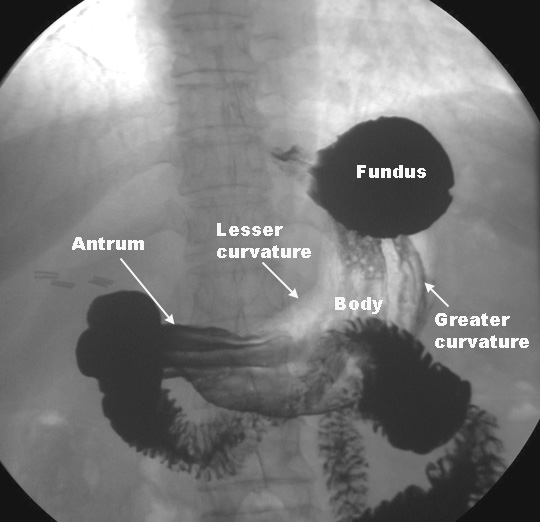

stomach parts fundus antrum curvature lesser gi cardia lumen meded luc curriculum radio edu pylorus